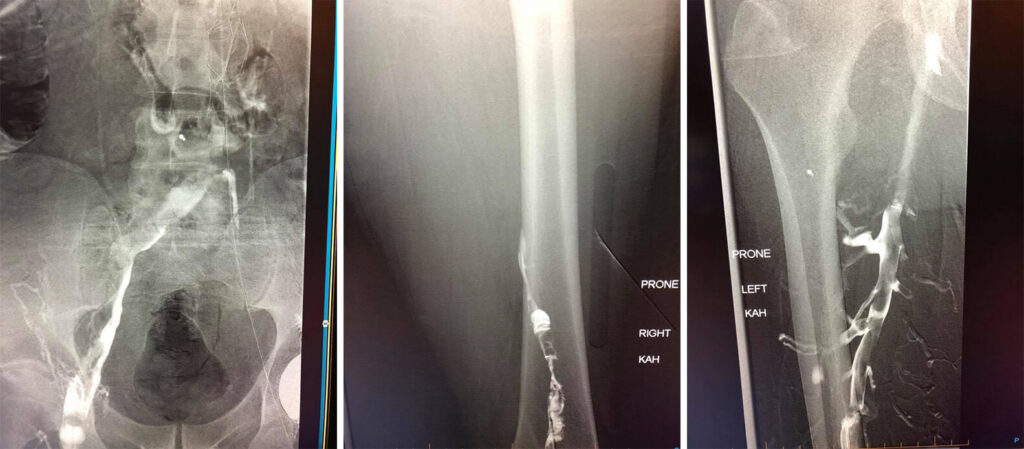

Case of the week: A 60 year old gentleman with extensive blood clots throughout both legs, pelvis and abdomen. Patient has an IVC filter with clot extending about the filter and acute clots into the lungs.

Day 1 venogram pictures shows occlusive deep vein thrombosis without any venous flow through the legs, pelvis or abdomen. Catheters were placed to drip clot busting drugs directly into the clot for 24 hours.

Day 2 venogram shows improved flow through the veins. Residual clot was then removed with special suction catheter (thrombectomy).